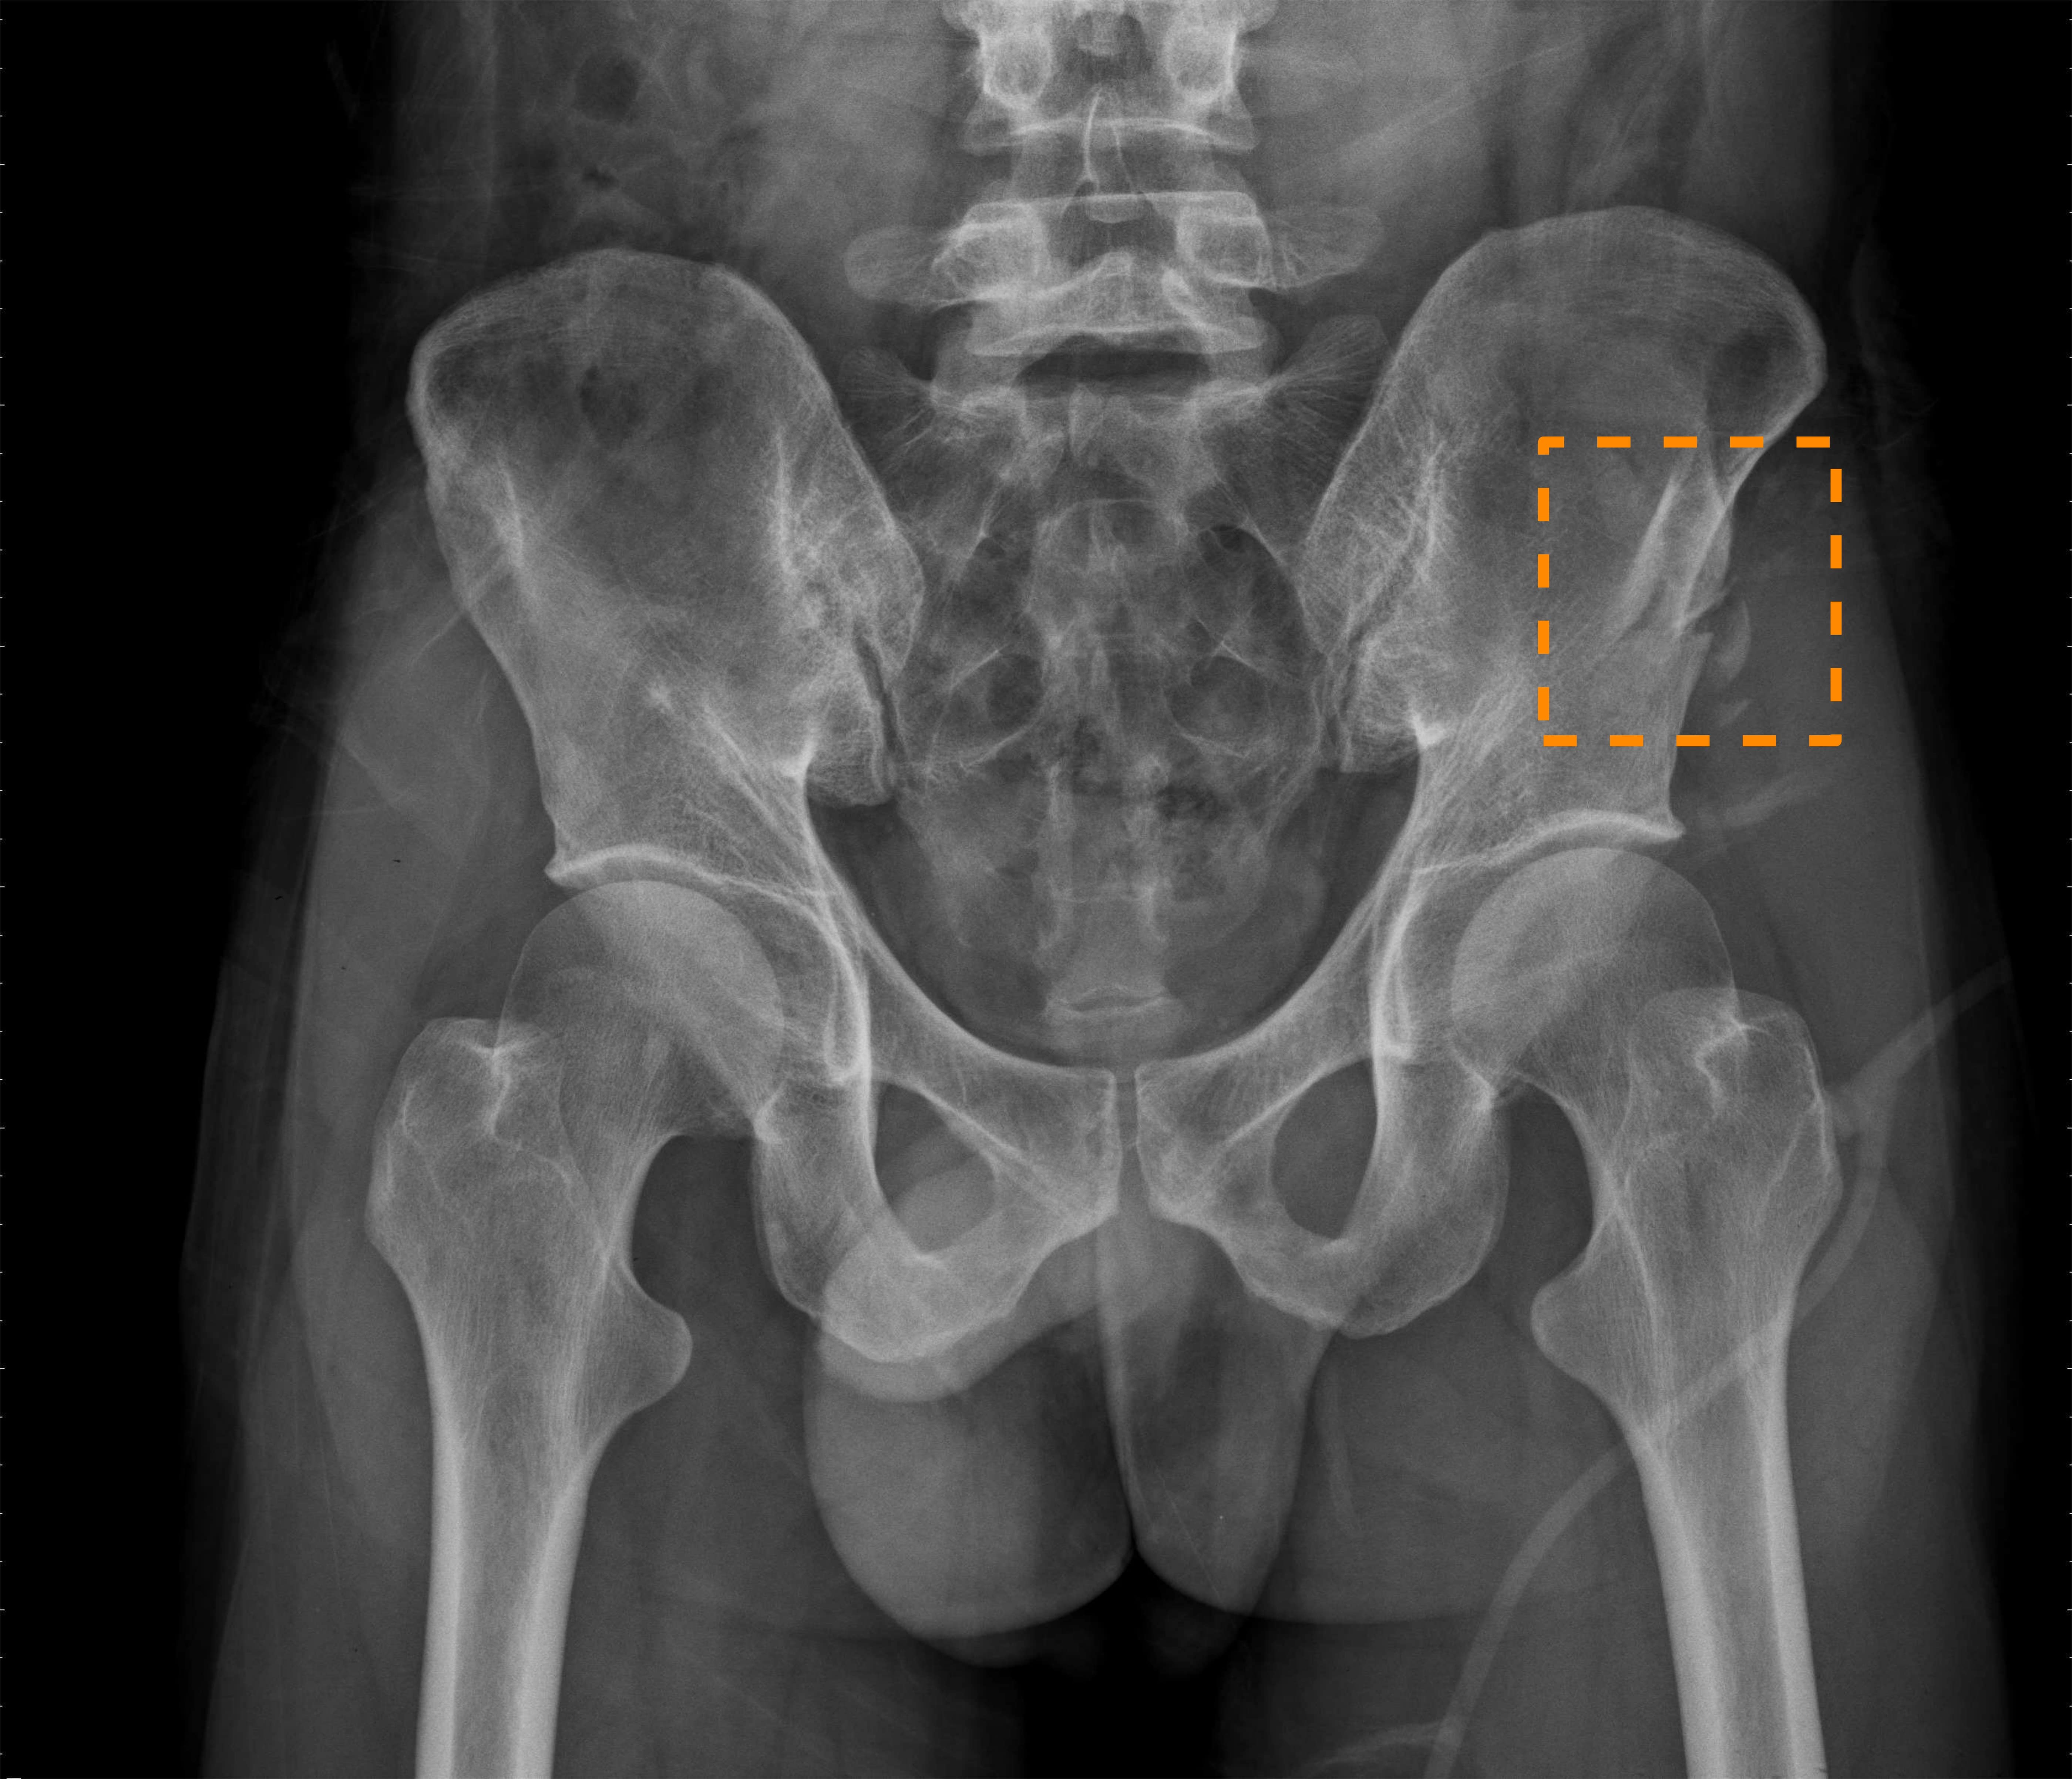

Nonetheless, the above prior work all only focuses on diagnosing hip fractures and does not attempt to classify the more complex pelvic fractures (fractures in three pelvic bones: the ilium, ischium, and pubis). As Fig. 1 illustrates, the makeup of pelvis fractures is much more complex, as there are a large variety of possible types with very different visual patterns at various locations. In addition, pelvic bones overlap with the lower abdomen, further confounding image patterns. Finally, unlike hip fractures, which occur at the femoral neck/head, pelvic fractures can occur anywhere on the large pelvis, both increasing the aforementioned image pattern combinatorial complexity and precluding automatic \acROI extraction based on anatomy alone, such as was done in prior work [4]. Thus, while using \acROI-based classification is even more desirable for pelvic fractures, it is paradoxically more challenging to extract said \acpROI.